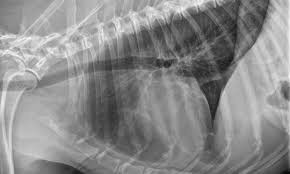

What Causes Spleen Cancer In Dogs - Spleen Cancer In Dogs Cats Long Beach Animal Hospital - Like many forms of cancer in dogs, we are unsure of the underlying cause of mast cell tumors, but certain breeds seem to be more at risk for developing them.;. Many other types of tumors, both benign and malignant, can occur in the spleen. The spleen is an organ that will store blood and will also supply blood to other organs, while cleaning blood cells as well. Often, owners do not realize their dog is affected until the sudden hemorrhage or collapse. This cancer is typically diagnosed via fine needle aspiration. If the above describes your dog's situation, then the immediate option is surgery.

Malignant lymphoma is one of the most common types of cancer that affects dogs. While the specific cause (s) for spleen cancer in dogs is unknown, we know that there must be some genetic factors, as certain breeds seem to be affected more than others. Hemangiosarcomas are fed by the blood vessels and fill with blood. Any large breed dog appears to be at an increased risk especially german shepherds, golden retrievers, labradors, and poodles. This cancer metastasizes at a rapid rate and affected dogs have limited survival time.

This cancer metastasizes at a rapid rate and affected dogs have limited survival time. Many other types of tumors, both benign and malignant, can occur in the spleen. Because of this, the tumor can rupture, leading to sudden and severe hemorrhage, collapse, and rapid death. It is the tumor of cells that line blood vessels, but most commonly affects heart, spleen, liver or skin. The spleen is an organ that will store blood and will also supply blood to other organs, while cleaning blood cells as well. Spleen and liver hemangiosarcoma in dogs. In some cases, one cause for the enlargement and inflammation of the spleen is a condition known as eosinophilic gastroenteritis. Hemangiosarcomas are fed by the blood vessels and fill with blood. Dogs with hemangiosarcoma in the spleen may not show any symptoms at the early stage. These causes include splenic torsion due to torsion causing the blood flow to be cut off, acute canine infectious hepatitis, salmonellosis and some types of spleen cancer (splenic lymphoma, splenic hemangiosarcoma). In this condition, cells and other substances from other parts of the body start to infiltrate into the spleen and cause an enlargement. This cancer is typically diagnosed via fine needle aspiration. If you notice your dog shedding pounds, either rapidly or slowly, make an appointment with your vet.

Https Encrypted Tbn0 Gstatic Com Images Q Tbn And9gctpw20aphku0gx0zqpgwvoc63jjsswrygculgbl Vkqndualo Usqp Cau from Lymphoma is a type of cancer that affects the lymphatic system. Cancer can also cause dogs to lose weight while maintaining their regular appetite. If you notice your dog shedding pounds, either rapidly or slowly, make an appointment with your vet. Mast cell tumors most commonly form nodules or masses in the skin, they can also affect other areas of the body, including the spleen, liver, intestine, and bone marrow. Spleen cancer occurs rarely in dogs and the causes of this disease are not entirely known. There are two main types of canine spleen cancer, hemangiomas and hemangiosarcomas. In dogs, the common primary sites for hemangiosarcoma are the spleen, the right atrium of the heart, and the subcutis, which is the tissue beneath the skin. This form of cancer is most common in the german shepherd, golden retriever and other large breeds.

This is a benign form of dog spleen cancer. The reason for this waxing and waning condition is due to the bleeding of the tumor. Malignant lymphoma is one of the most common types of cancer that affects dogs. Sometimes, dog owners don't realize their pets have the cancer until they suddenly pass away without warning. Treatment in dogs with either a splenic tumour or ruptured spleen is usually surgical removal of the whole organ. Dog mast cell tumors are one of the most common forms of dog skin cancer. Hemangiosarcomas are fed by the blood vessels and fill with blood. This is one of the most dangerous tumors in dogs. Hemangiosarcoma is an incurable malignant cancer forming a tumor or tumors in the cells that form the inner lining of blood vessels and can occur in the liver or spleen. This cancer metastasizes at a rapid rate and affected dogs have limited survival time. It is a cancer made up of the cells that line blood vessels, and therefore can be found in any part of the body. Like many forms of cancer in dogs, we are unsure of the underlying cause of mast cell tumors, but certain breeds seem to be more at risk for developing them.; When a tumor grows on a dog's spleen, it is always one of two forms.

It is the tumor of cells that line blood vessels, but most commonly affects heart, spleen, liver or skin. Spleen and liver hemangiosarcoma in dogs. This is one of the most dangerous tumors in dogs. Many dogs will experience enlargement of the lymph nodes in one or more parts of the body. It is a cancer made up of the cells that line blood vessels, and therefore can be found in any part of the body. Often, owners do not realize their dog is affected until the sudden hemorrhage or collapse. If the above describes your dog's situation, then the immediate option is surgery. Sometimes this cancer may cause weakness, especially in the hind legs, and decreased energy that lasts for a day or two, then goes away only to reappear weeks or months later. In both cases, the mass forms out of the soft tissue creating what looks a lot like a blood blister. Cancer can also cause dogs to lose weight while maintaining their regular appetite. This cancer metastasizes at a rapid rate and affected dogs have limited survival time. In dogs, red blood cells are the actual source of spleen cancer. Hemangiosarcomas are fed by the blood vessels and fill with blood.